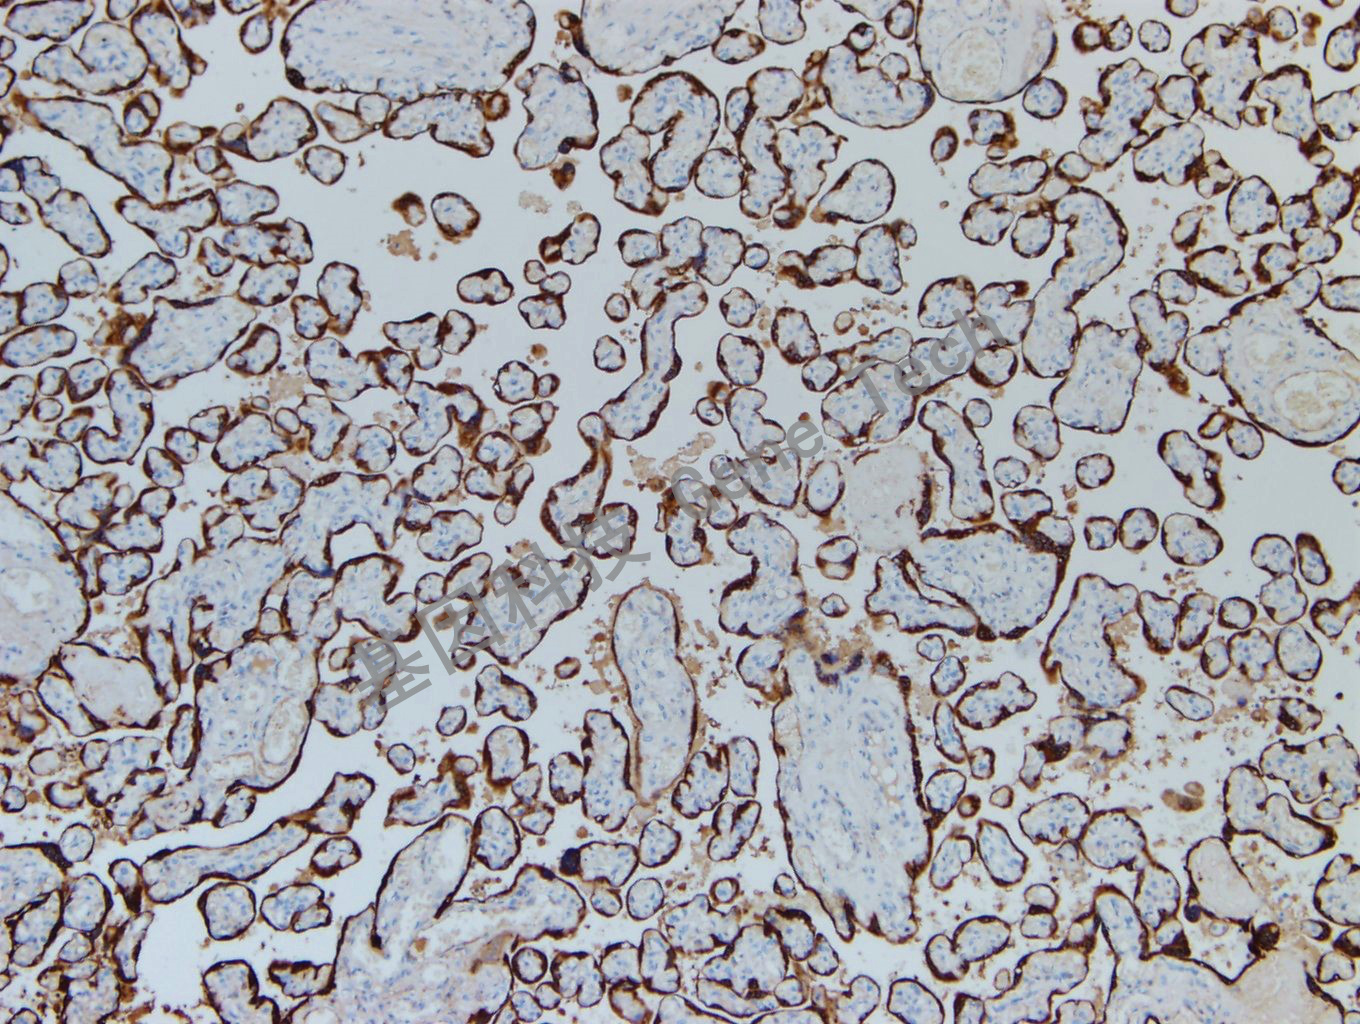

HPL 兔抗人 Human Placental Lactogen 抗體試劑(免疫組織化學(xué))

| 克隆號(hào):GR321 | 種屬:兔 | 適用染色系統(tǒng):GTvisionTM |

| 預(yù)處理:無需修復(fù) | 陽性部位:細(xì)胞漿 | 陽性對(duì)照:胎盤 |

| 簡(jiǎn)介:HPL(Human placental lactogen, 人胎盤催乳素)是胎盤合體滋養(yǎng)層細(xì)胞合成和分泌的一種多肽激素,主要用于絨毛膜癌、睪丸癌、乳腺癌和卵巢癌的惡性畸胎瘤的診斷和少數(shù)具有異位性激素分泌的腫瘤(如肺癌)的研究。 | ||

| 胎盤石蠟切片,用 HPL(GT2205)染色,細(xì)胞漿陽性,DAB 顯色。 | ||